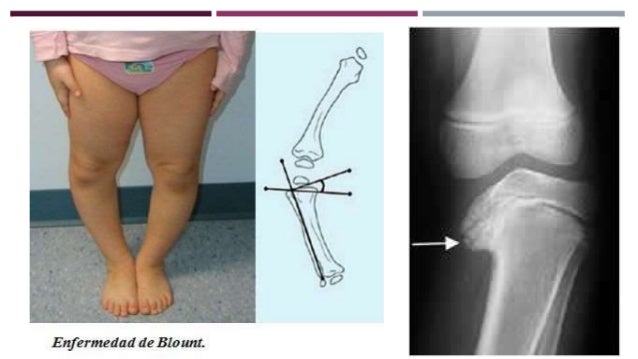

Enfermedad de blount radiologia. La enfermedad de Blount se caracteriza por una alteración del crecimiento de la parte interior del extremo superior de la tibia, que evoluciona progresivamente produciendo unas piernas arqueadas con una desviación ósea justo por debajo de la rodilla (tibia varus) En el 60% de los casos hay afectación de ambas piernas. TIBIA VARA ENFERMEDAD DE BLOUNT Conocida también como osteocondritis deformante de la tibia, la enfermedad de Blount, descrita en 1937, es una deformidad en varo proximal de la tibia Por ser una forma patológica de genu varum, creemos que merece una capitulación aparte Etiología. Hallazgo que le haría acreedor del Premio Nobel de Física en 1901.

La enfermedad de Blount conduce a artrosis precoz, paradójicamentees más frecuente en el compartimento femorotibial externo que en el interno, debido a contractura en exión de. RESUMEN Fundamento la enfermedad de Blount afecta la metafisis interna de la tibia superior y se caracteriza por presentación clínica de tibia vara, puede ser unilateral o bilateral y estar asociada a torción tibial interna Objetivo presentar un caso de enfermedad de Blount la cual fue diagnosticada en consulta externa por medio del examen clínico y radiografías. Por el contrario, la enfermedad de Blount no se corrige, todo lo contrario, empeora conforme va pasando el tiempo De ahí que sea tan importante que la misma pueda ser detectada cuanto antes en.

La enfermedad de Blount o tibia vara es una alteración del desarrollo que afecta al cartílago de crecimiento proximal de la tibia Es una entidad poco frecuente y de probable origen multifactorial, cuya etiología no está aclarada Provoca una deformidad progresiva con un arqueamiento de las extremidades inferiores en forma de genu varo En la variante precoz es más frecuente la. Enfermedad de Blount Article Translations La Enfermedad de Blount es un trastorno del crecimiento que afecta a los huesos de la parte inferior de la pierna y los hace curvarse hacia afuera En los niños más pequeños, solo se ve afectada la tibia En los adolescentes, se suele ver afectada tanto la tibia como el fémur. La enfermedad de membrana hialina (EMH) es un cuadro de dificultad respiratoria grave y progresiva que se produce fundamentalmente en recién nacidos prematuros Se presenta aproximadamente en el 5 a 10 % de los niños nacidos antes del término del embarazo, siendo más frecuente a mayor prematuridad.

Sección de Radiología Músculoesquelética del Servicio de Diagnóstico por La forma infantil de la enfermedad de Blount, que se produce en niños un poco más mayores, suele ser bilateral(1,3,11), la fisis tibial proximal es irregular y la metáfisis me. La radiología es el uso médico de la radiación para diagnosticar y tratar diversos problemas de salud A partir de la utilización de rayos gamma, rayos X y otras clases de rayos, es posible obtener imágenes internas del organismo Lo habitual es que las imágenes que ofrece la radiología sean empleadas para diagnosticar una enfermedad En ciertos casos específicos, la radiología. Enfermedades que trata el Servicio de Radiología Encuentra información sobre las enfermedades que tratamos en el Servicio de Radiología Aprende a cuidar y cuidarte Pulsa la primera letra del tema que quieres buscar.

Discusión Langesnskiöld 19(1) distinguió cuatro tipos de tibia vara tibia vara infantil (enfermedad de Blount), tibia vara del adolescente, tibia vara de inicio tardío y la causada por displasia fiSección de Radiología Músculoesquelética del Servicio de Diagnóstico por Imagen del Hospital de Traumatología y Rehabilitación de. Enfermedad de Blount Tibia 518 Enfermedad de Sever Calcáneo 10 Enfermedad de Thiemann Falanges de las manos 1119 exploración física y exploraciones complementarias como la radiología de perfil de la columna, que serían suficientes para llegar a este diagnóstico Bibliografía. En un reciente metaanálisis se observó que los pacientes con enfermedad de Blount de aparición temprana son más propensos a tener un compromiso bilateral 1 Se ha observado una predisposición en la raza negra, y existe una posible asociación con alteraciones metabólicas como déficit de vitamina D 1, 2, 3.

Enfermedad de Blount Tibia vara Genu varo Obesidad Resumen Abstract Blount disease a case report La enfermedad de Blount o tibia vara es una alteración del desarrollo que afecta al cartílago de crecimiento proximal de la tibia Es una entidad poco frecuente y de probable origen multifactorial, cuya etiología no está aclarada. Tratamiento de la enfermedad de OsgoodSchlatter o crecederas El tratamiento de las crecederas generalmente suele ser sintomático , ya que es una patología que con la disminución de la actividad e intensidad física, junto con estiramientos y normalización de la musculatura del miembro inferior para reducir la tensión que llega a la tibia. Y adolescente, que afecta a los niños más grandes y adolescentes.